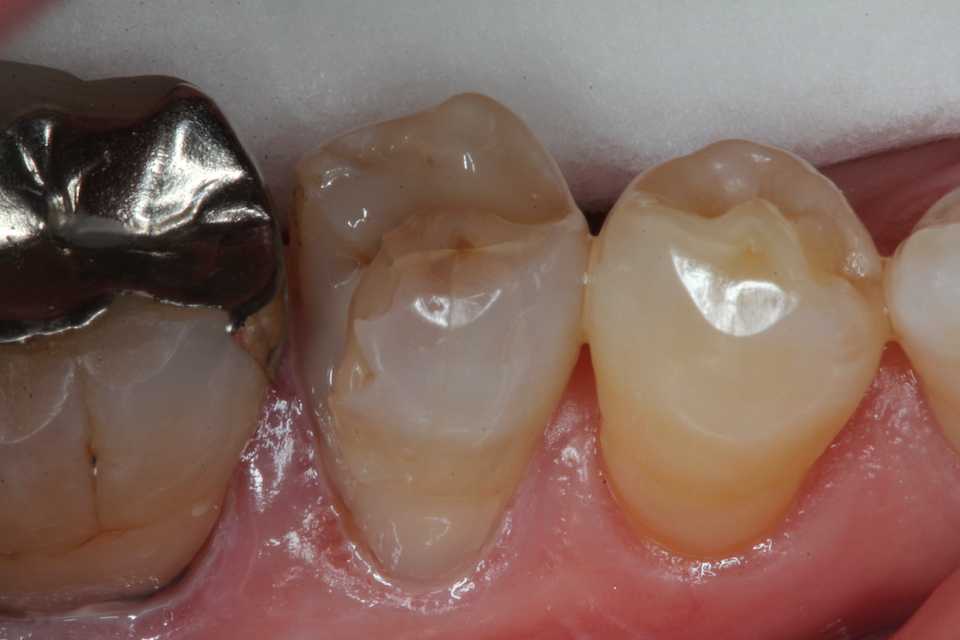

50代女性、右下5、インレー2次カリエス

では時系列でどうぞ